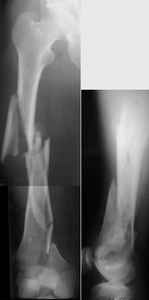

A new toy is more interesting and fashionable. And anyway it is not panacea, i have already seen presentations with LISS failures like the attached one presented by D.Seligson. And people also demonstrated incisions say that the method is not so LESS invasive as it supposed to be.

Отправитель: Enes M. Kanlic 13 Ноябрь 2004, 19:43

Attached are few examples from our Hospital:

Malpositioning is much too common (recurvatum, varus - valgus).

B. Fixation loosening: distal cutting of the nail, non-unions do happen (cases attached).